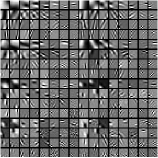

Fig. 1 shows example transforms (rows of are reshaped as patches and the first slices of such 3D patches are shown) learned from patches of an XCAT phantom [54] volume. The transform learned with in (P0) has more oriented features whereas the transform learned with shows more gradient (or finite-difference) type features (pointed by the green arrows). This behavior suggests that a single ST may not be rich enough to capture the diverse features, edges, and other properties of CT volumes. Therefore, next we consider the extension of the ST approach to a rich union of learned transforms scheme.

Fig.Β 3 presents an example of the pixel-level clustering in the central axial slice achieved with the PWLS-ULTRA method for . Since PWLS-ULTRA clusters patches, we cluster individual pixels using a majority vote among the 3D patches that overlap the pixel. Class contains most of the soft tissues; class comprises most of the bones and blood vessels; classes and have some high-contrast edges oriented along specific directions; and class mainly includes low-contrast edges. Since the clustering step (during both training and reconstruction) is unsupervised, i.e., different anatomical structures were not labeled manually, there are also a few edges with high pixel intensities included in class . The trained (3D) transforms (with ) for each cluster are also displayed in a similar manner as in Fig.Β 1. The transforms show features (e.g., with specific orientations) that clearly reflect the properties of the patches/tissues in each class.

Recall that in Section IV.F, we used the transforms learned from the patches of the XCAT phantom volume to perform reconstruction of the chest volume from helical CT data. Alternatively, one could learn the transforms from the patches of the PWLS-EP reconstruction of the helical CT data. Fig.Β 14 shows the union of transforms () learned from patches of the XCAT phantom and the PWLS-EP chest reconstruction, with . These two union of transforms display some similar types of features, and provide similar visual reconstructions in PWLS-ULTRA (with patch-based weights ) in Fig.Β 14. Thus, the transform learning algorithm extracts quite general and effective sparsifying features for images, without requiring a very closely matched training dataset.